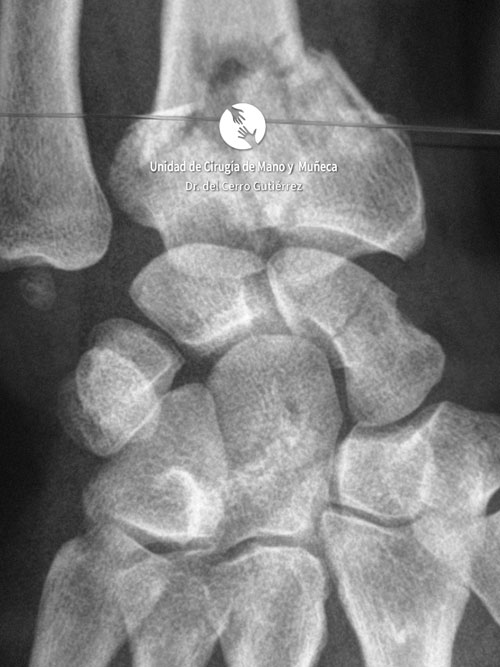

Imágenes de diagnótico de fracturas del radio distal de la muñeca

Fractura del Radio. Avulsión Estiloides.

Fractura del Radio. Desplazamiento Dorsal.

Fractura del Radio. Fractura Extraarticular

Fractura del Radio.

Fractura del Radio. Fractura del Escafoides.

Fractura del Radio. Conminuta y Articular.